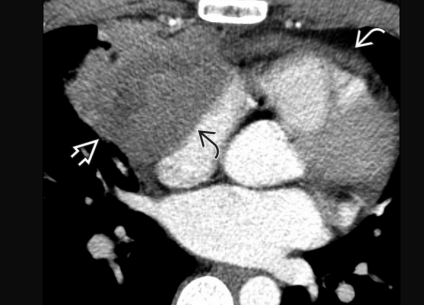

Metastases de mélanome VD et OD

Metastases de mélanome VD et OD

Metastase myocardique melanome progressif

Metastase myocardique melanome progressif